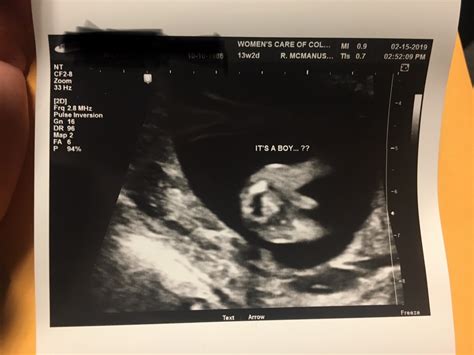

• Can I find out the baby's gender at 13 weeks? Determining the baby's gender is typically more accurate after 18-20 weeks of pregnancy. At 13 weeks, the genitalia may not be fully developed, making it difficult to determine the gender accurately.

• Fetal Measurements: The healthcare provider will measure the baby's crown-rump length (CRL), which is the distance from the top of the head to the bottom of the buttocks. This measurement helps determine the baby's gestational age and growth rate.

• Anatomy Check: The ultrasound will assess the baby's anatomy, including the brain, spine, heart, kidneys, and limbs. This check helps identify any potential abnormalities.